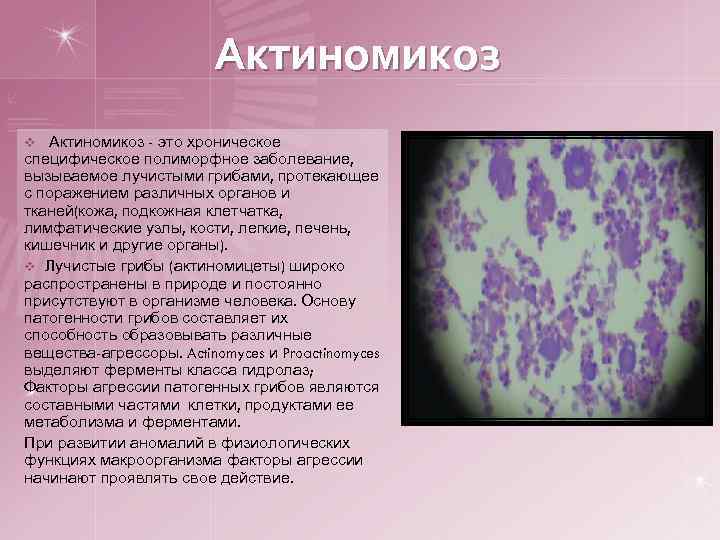

Актиномикоз - это хроническое специфическое полиморфное заболевание, вызываемое лучистыми грибами, протекающее с поражением различных органов и тканей(кожа, подкожная клетчатка, лимфатические узлы, кости, легкие, печень, кишечник и другие органы). v Лучистые грибы (актиномицеты) широко распространены в природе и постоянно присутствуют в организме человека. Основу патогенности грибов составляет их способность образовывать различные вещества-агрессоры. Actinomyces и Proactinomyces выделяют ферменты класса гидролаз; Факторы агрессии патогенных грибов являются составными частями клетки, продуктами ее метаболизма и ферментами. При развитии аномалий в физиологических функциях макроорганизма факторы агрессии начинают проявлять свое действие. v